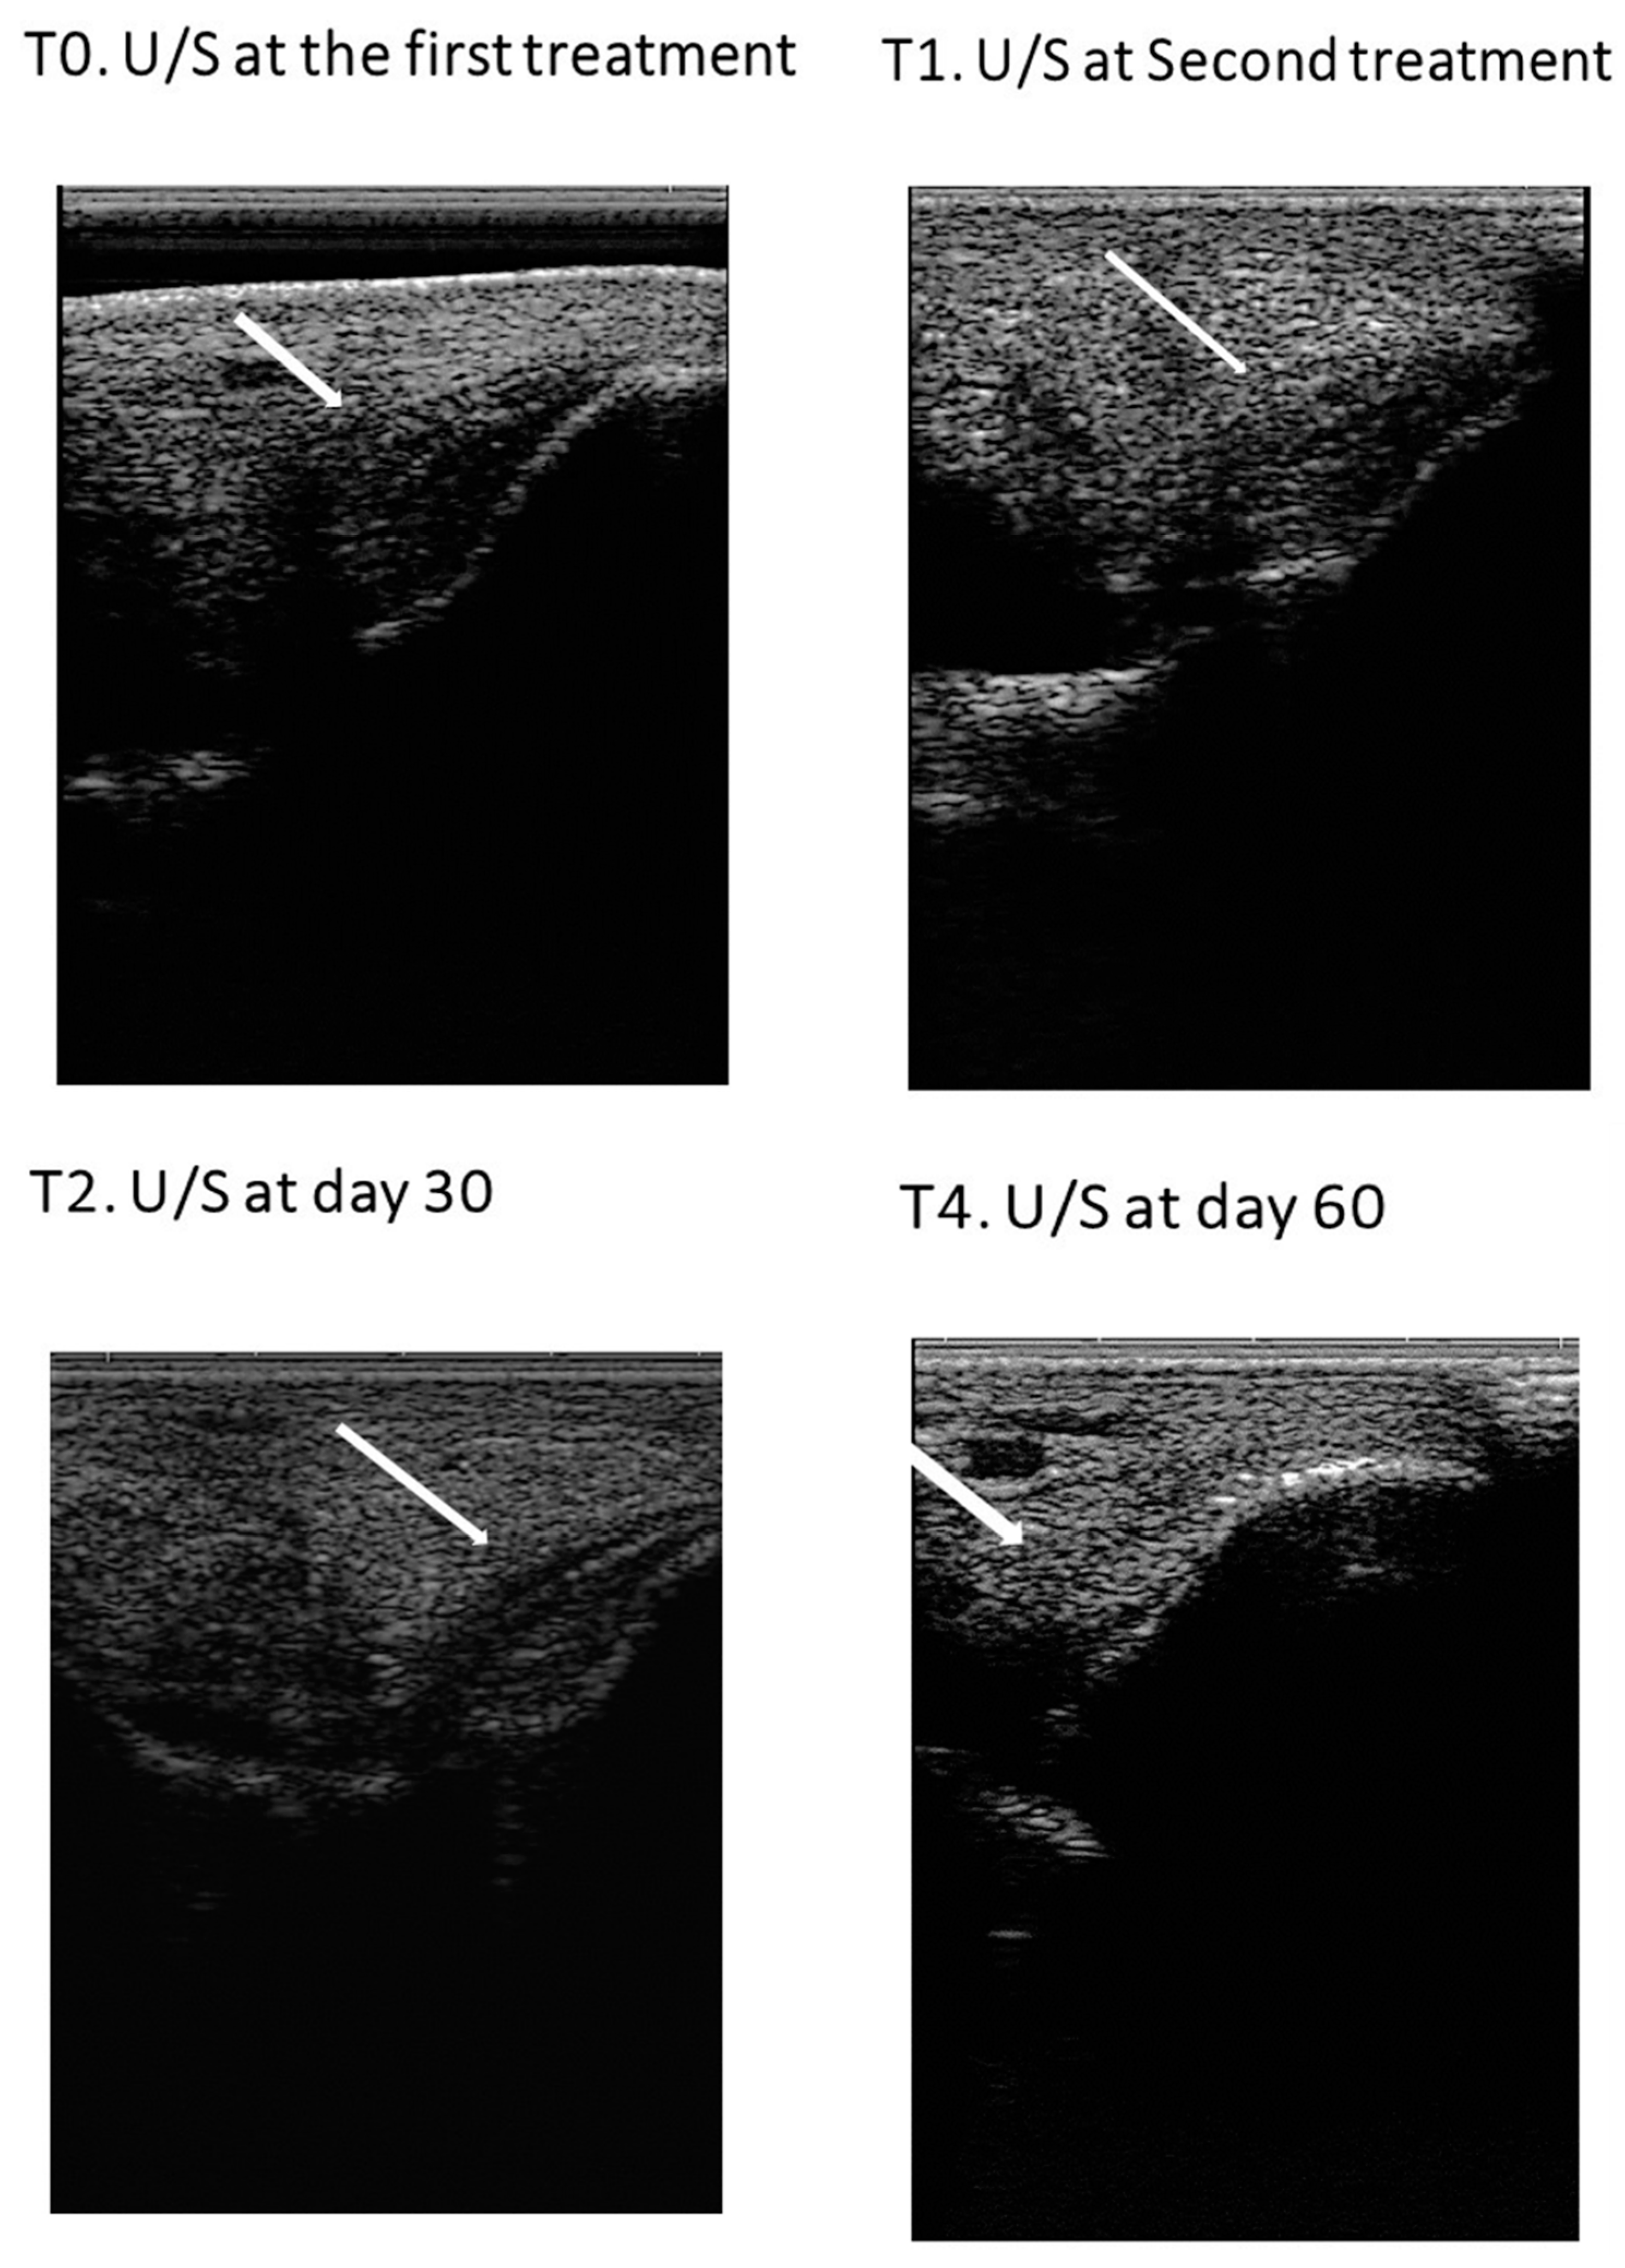

3.1.2. Ultrasound examination

3.4. Treatment Results